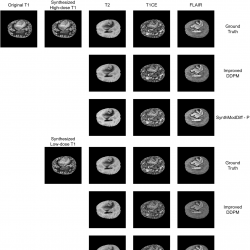

Fig. 3

Qualitative comparison of synthetic modality generation (T2, PD, and MRA) from a T1 input image on the IXI dataset. The figure follows the same layout as Fig.

2, enabling a direct comparison between ground truth, Improved DDPM, and SynthModDiff under different dose conditions.

Figures

2 and

3 illustrate qualitative results for the task of synthetic modality generation from a single T1-weighted input image. In both figures, the first column shows the input T1 image, while the subsequent columns correspond to the synthesized target modalities, namely T2, T1CE, and FLAIR for BraTS2020 (Fig.

2), and T2, PD, and MRA for the IXI dataset (Fig.

3).

For each target modality, the first row represents the ground truth image acquired at the corresponding modality. The second and third rows present the synthesis results obtained using the second-best baseline method (Improved DDPM) and the proposed SynthModDiff method, respectively. This layout is repeated for two different input conditions: synthesized high-dose T1 (upper block) and synthesized low-dose T1 (lower block), allowing a direct comparison of robustness under varying noise levels.

As the dose level decreases, both methods exhibit some degradation due to increased noise in the input T1 image. However, Improved DDPM tends to produce overly smoothed results and fails to preserve modality-specific contrast, leading to blurred anatomical boundaries and reduced visibility of fine structures. In contrast, SynthModDiff consistently generates target modalities that are visually closer to the ground truth, preserving critical anatomical details and contrast patterns across different modalities. Notably, structures such as tissue boundaries, lesion regions, and vascular or bone-related details remain more distinguishable in SynthModDiff results, even under low-dose conditions.

These observations demonstrate that SynthModDiff is more robust for synthetic modality generation, particularly when the input modality is affected by reduced dose levels, which is crucial for practical clinical scenarios where minimizing radiation exposure is essential.